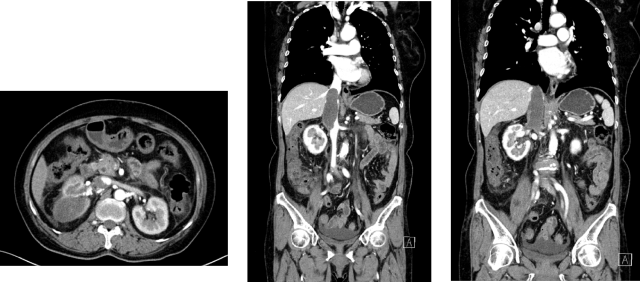

<p><strong>摘要</strong></p><p>女性，64 岁<br/>主诉：血尿1周，检查发现右肾肿瘤，于 2023-06-17 就诊于我科<br/>查体：浅表淋巴结未触及肿大，心、肺、腹（-）<br/>ECOG 评分：1 分<br/>既往史：子宫肌瘤术后 20 年；神经衰弱病史 1 年，佐匹克隆治疗；高血压病史 20 年，硝苯地平、利血平治疗。</p><p><strong><br/></strong></p><p><strong>临床资料</strong></p><p>一、辅助检查</p><p>肾脏 MR 平扫＋动态增强：右肾中上份为主见类椭圆形等 T1 等 T2 信号肿物，截面约 8.0×6.5cm，T1WI 反相位部分区域信号强度减低，DWI 及 ADC 扩散受限，呈不均匀快进快出强化模式；病灶侵及部分右肾静脉-下腔静脉，以上水平下腔静脉全程粗大，可见团状不均匀强化充盈缺损，肝中静脉内见条状充盈缺损区，符合右肾恶性肿瘤（CCRCC 可能大）累及部分右肾静脉并下腔静脉瘤栓，肝中静脉栓子形成 MR 表现。</p><p>病理：2023-06-19 行右肾穿刺活检术：（右肾占位穿刺）符合透明细胞性肾细胞癌。 免疫组化：CA9（+），Vimentin（+），CK7（-），TFE3（-），FH（+），PAX8（+），CD117（-）。</p><p>2023-06-14 泌尿系 CTU 增强：右肾及下腔静脉内富血供肿块，右肾癌并腔静脉癌栓达膈肌以上，肾占位最大横截面 9.9*6.1cm，腔静脉占位最大横截面 6.1cm，上下范围 12.4cm，可见肝静脉栓子。</p><p style="text-align: center;"><img src="https://img1.dxycdn.com/p/s10/2025/1124/477/6332268857029482991.png!w640" alt="图片1.png"/></p><p>二、诊断与鉴别诊断</p><p>初步诊断：右肾透明细胞癌并腔静脉瘤栓；肝静脉癌栓</p><p>分期：cT3bN0M0</p><p><br/></p><p><strong>治疗情况</strong></p><p>2024-09-13 ： 胸部+全腹部(含盆腔）CT 平扫+增强 ：右肾中上份见一类椭圆形略低密度灶，较大截面约 5.5×4.0cm，边界欠清，增强扫描呈欠均匀轻度强化，较前增大，病灶侵及部分右肾静脉-下腔静脉，以上水平下腔静脉全程粗大，较宽处约 3.8cm。右肾恶性肿瘤并右肾静脉、下腔静脉治疗后 CT 所见。</p><p>2024-11-01： 胸部+全腹部(含盆腔）CT 平扫+增强 ：右肾中上份见一类椭圆形略低密度灶，较大截面约 5.5×4.0cm，边界欠清，增强扫描呈欠均匀轻度强化，较前变化不明显，病灶侵及部分右肾静脉-下腔静脉，以上水平下腔静脉全程粗大，较宽处约 3.8cm 右肾恶性肿瘤并右肾静脉、下腔静脉治疗后CT所见，较前变化不明显 SD。<br/>胃肠道反应较重，恶心纳差乏力伴声音嘶哑反应较重，高血压，AE3 级。</p><p>2024-11-01：再次换用舒尼替尼 50mg，2-1 方案；<br/>消化道不良反应较重，恶心呕吐重，1 周内住院两次，AE3 级。</p><p>2024-11-15：换伏罗尼布 200mg po qd+艾帕洛利托沃瑞利单抗注射液。</p><p>2024-09-13：</p><p style="text-align: center;"><img src="https://img1.dxycdn.com/p/s10/2025/1124/538/0650772702832582991.png!w640" alt="图片2.png"/></p><p>2024-11-01：</p><p style="text-align: center;"><img src="https://img1.dxycdn.com/p/s10/2025/1124/788/4220497517252582991.png!w640" alt="图片3.png"/></p><p>2024-11 至今：伏罗尼布 200mg po qd+ 艾托组合抗体</p><p>CT复查：2025-02-07，胸部+全腹部(含盆腔）CT 平扫+增强 ：右肾中上份见一类椭圆形略低密度灶，较大截面约 4.6×3.8cm，边界欠清，增强扫描呈欠均匀轻度强化，较前变化不明显，病灶侵及部分右肾静脉-下腔静脉，以上水平下腔静脉粗大，较宽处约 3.8cm，右肾恶性肿瘤并右肾静脉、下腔静脉癌栓治疗后 CT 所见，癌栓位于膈肌下 2cm，肝静脉癌栓消失（PR）。</p><p>AE：irAE 甲状腺功能减退（对症治疗效果好）；肝功轻度异常；未见其他明显不良反应。</p><p><img src="https://img1.dxycdn.com/p/s10/2025/1124/146/8258361971504582991.png!w640" alt="图片5.png"/></p><p><img src="https://img1.dxycdn.com/p/s10/2025/1124/089/4646237200034582991.png!w640" alt="图片6.png"/></p><p><br/></p><p><strong>病例1：新辅助可能性讨论</strong></p><p>肾癌新辅助治疗的手术获益：从不可切除到部分切除的转变。</p><p>场景一：不可切除的肿瘤变得可以切除（癌栓等）</p><ol class=" list-paddingleft-2" style="list-style-type: decimal;"><li><p>巨大、复杂，侵犯肾蒂血管，淋巴结融合成团，高级别腔静脉瘤栓，周围重要器官受侵犯，手术风险高；</p></li><li><p>新辅助治疗有助于瘤栓降级、降低手术难度；合并癌栓的肾癌选择应用新辅助治疗为无法手术的患者再次赢得手术机会。</p></li></ol><p>场景二：不可部分切的肿瘤变得可以部分切除（保肾、高难度保肾）</p><ol class=" list-paddingleft-2" style="list-style-type: decimal;"><li><p>在控制切缘阳性率的同时尽可能保肾；保留肾单位手术（PN）结合使用时增强肾脏功能保留，这对于局部晚期RCC的治疗至关重要；</p></li><li><p>通过术前新辅助治疗，可以使肿瘤体积缩小，增加手术切除的成功率，提高肾癌患者的生存率，帮助双侧肾癌及孤立肾患者行保留肾单位手术或行根治性切除术。</p></li></ol><p>其他优势</p><ol class=" list-paddingleft-2" style="list-style-type: decimal;"><li><p>测试药物敏感度，为晚期阶段系统治疗药物选择提供参考；</p></li><li><p>调节免疫微环境，增加免疫反应，改善免疫抑制的肿瘤微环境。</p></li></ol><p>专家共识建议：减少因为不良反应而中断治疗的比例，更有益于患者的生存获益与生命质量的提高。</p><p><img src="https://img1.dxycdn.com/p/s10/2025/1124/709/8041462239455582991.png!w640" alt="图片7.png"/></p><ul class=" list-paddingleft-2" style="list-style-type: disc;"><li><p>靶向药物治疗肾癌时不良反应的管理非常重要。减少因为不良反应而中断治疗的比例更有益于患者的生存获益与生命质量的提高。</p></li><li><p>若出现 Ⅲ 级皮肤症状（重度皮肤改变，伴疼痛，影响个人日常生活），则应中止靶向治疗 1～2 周，必要时请皮肤科会诊，改善皮肤症状恢复至 0～I 级，方可考虑恢复靶向药物的使用。</p></li><li><p>转氨酶&gt;3×ULN 和总胆红素&gt;2×ULN 应停止治疗，且对患者持续进行监测，直至氨基转移酶恢复至1级或基线；若转氨酶水平&gt;8×ULN 应立即停止治疗，纠正肝功能后考虑其他靶向药物。若转氨酶水平＞8×ULN 应立即停止 治疗，纠正肝功能后考虑其他靶向药物。</p></li></ul><p><strong><br/></strong></p><p><strong>伏罗尼布--首个拥有中国自主知识产权肾癌小分子靶向自主创新药</strong></p><p>亲和力高：分子结构设计上，通过引入二甲胺基甲酰基（C=O）与 VEGFR 形成额外氢键，引入S-构型吡咯烷基分子构型固定，增加靶点亲和力。</p><p>组织蓄积毒性低：「二甲胺基甲酰基」碱性降低，降低了磷脂生物膜的穿透性，降低了组织分布，避免了组织蓄积毒性。</p><p>易代谢：「二甲胺基甲酰基吡咯烷基」具有更多的体内代谢位点，伏罗尼布和其 N-脱甲基代谢产物 X-297 具有更快的体内清除速率，消除相半衰期更短，可实现靶点的间歇抑制，降低毒性。</p><p><strong><br/></strong></p><p><strong>伏罗尼布单药——安全性良好，患者更易耐受</strong></p><p><img src="https://img1.dxycdn.com/p/s10/2025/1124/152/4872430269666582991.png!w640" alt="图片8.png"/></p><p><strong><br/></strong></p><p><strong>小结</strong></p><p>1、晚期肾癌进入靶免治疗时代，但靶向治疗依旧是重要的选择；无论靶向还是靶免一线治疗，药物不耐受普遍存在。中国回顾性研究发现，约 24.6% 的患者因无法耐受不良反应终止一线治疗。</p><p>2、伏罗尼布是中国肾癌治疗领域首个具有中国自主知识产权的创新药物，具有更强的靶点亲和力，毒性更小，组织蓄积性更低。</p>              ]]>